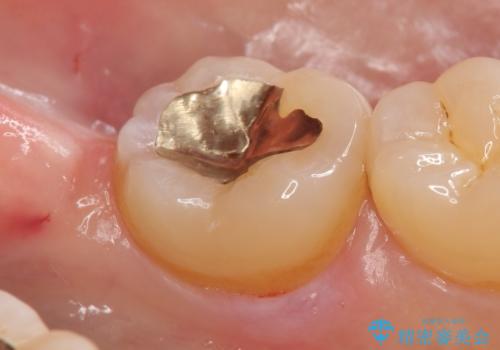

- 右下の奥歯が冷たいものを飲むとしみるので診て欲しいといらっしゃった方の症例です。

古い樹脂を除去し、PGA(ゴールド)インレーによる修復を行いました。

- PGA(ゴールド)インレー…¥60,000費用は治療当時の料金となります